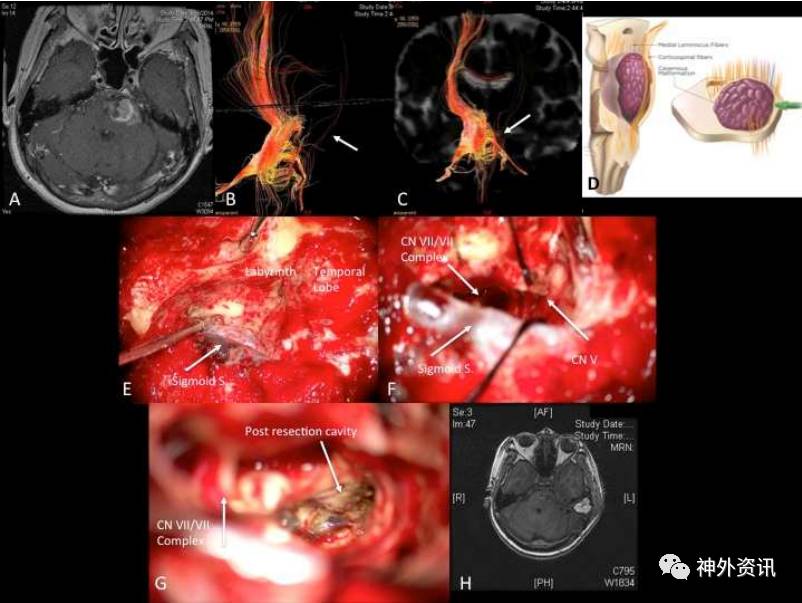

图3. 1例左侧桥脑CM的63岁女性患者。A.水平位MRI显示左侧桥脑大型CM;B、C.DTI三D重建的前方和前外侧的皮质脊髓束(小箭头);D.与CM和皮质脊髓束相对应的示意图,提示前入路手术风险较高,选择靠后的入路;E.术中照片示,左侧迷路后乙状窦前入路;F.术中照片可见病变,予切除;G.术中照片示,CM完全切除(箭头);H.术后MRI显示病灶全切。